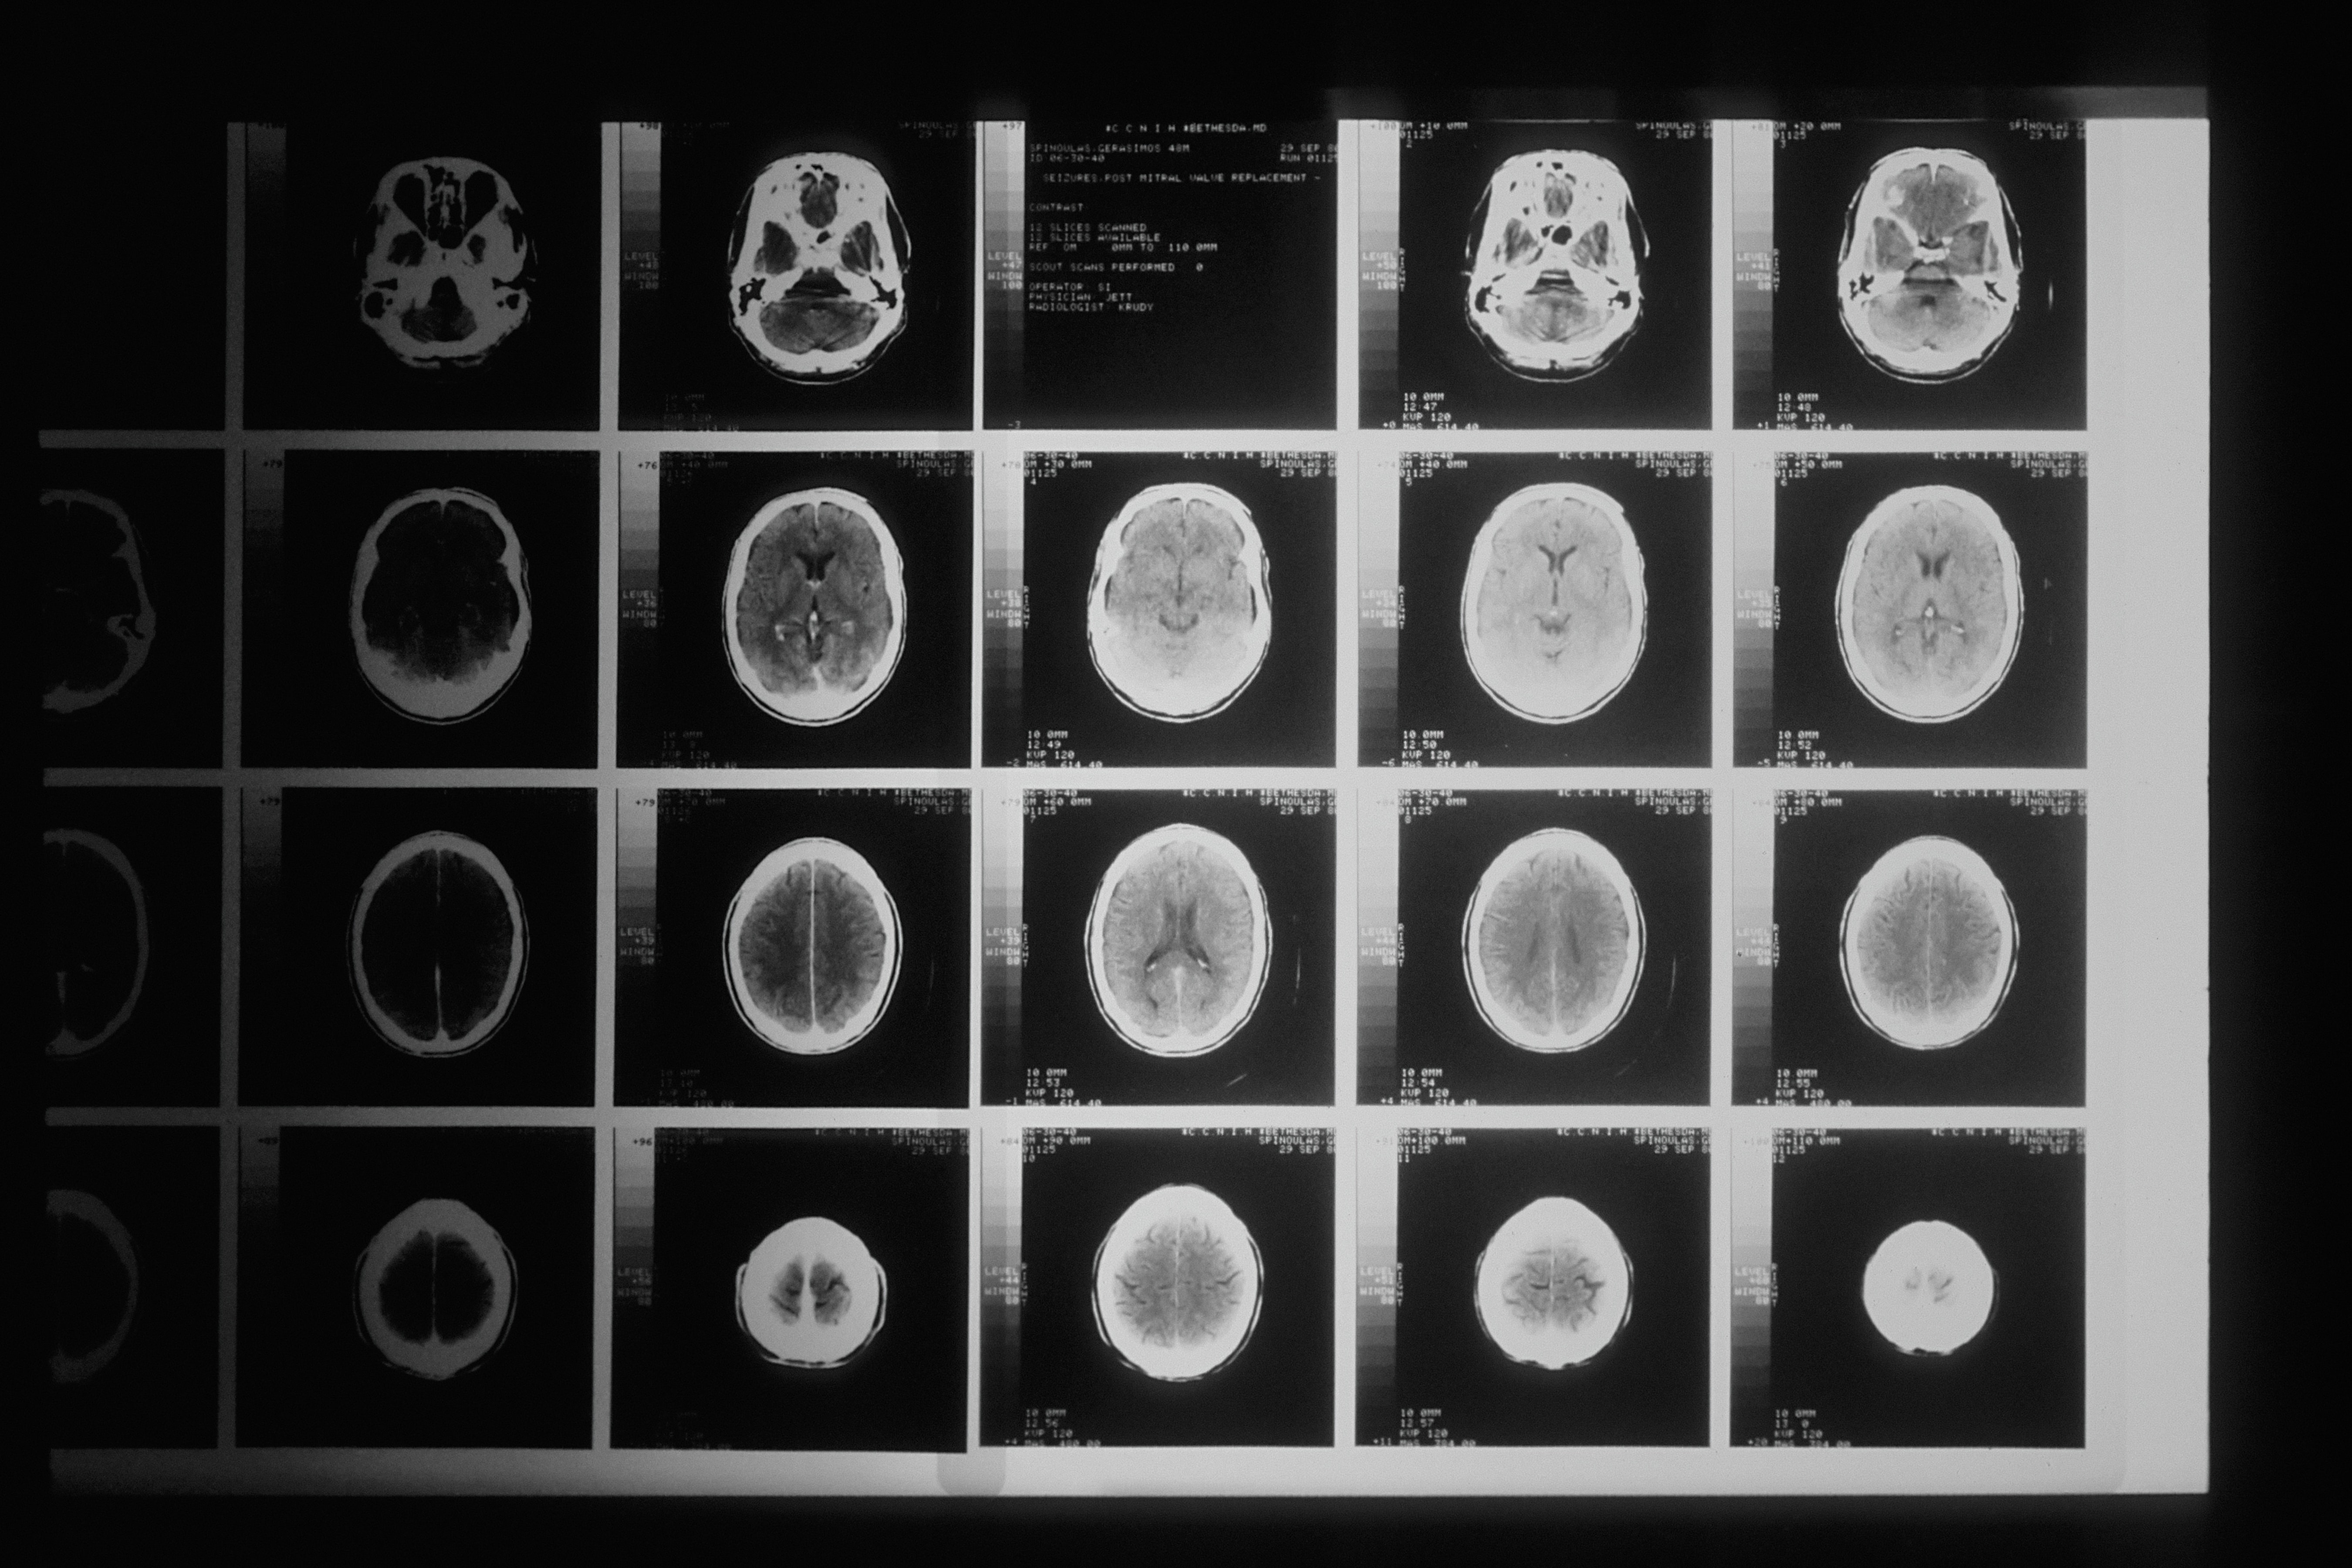

In order to sue for your brain injury, you’ll need to prove that it actually occurred in the first place. When you receive medical attention for your brain injury, you may be “graded” according to the Glasgow Coma Scale. This is a standardized system used by medical professionals to determine how severe a brain injury is.